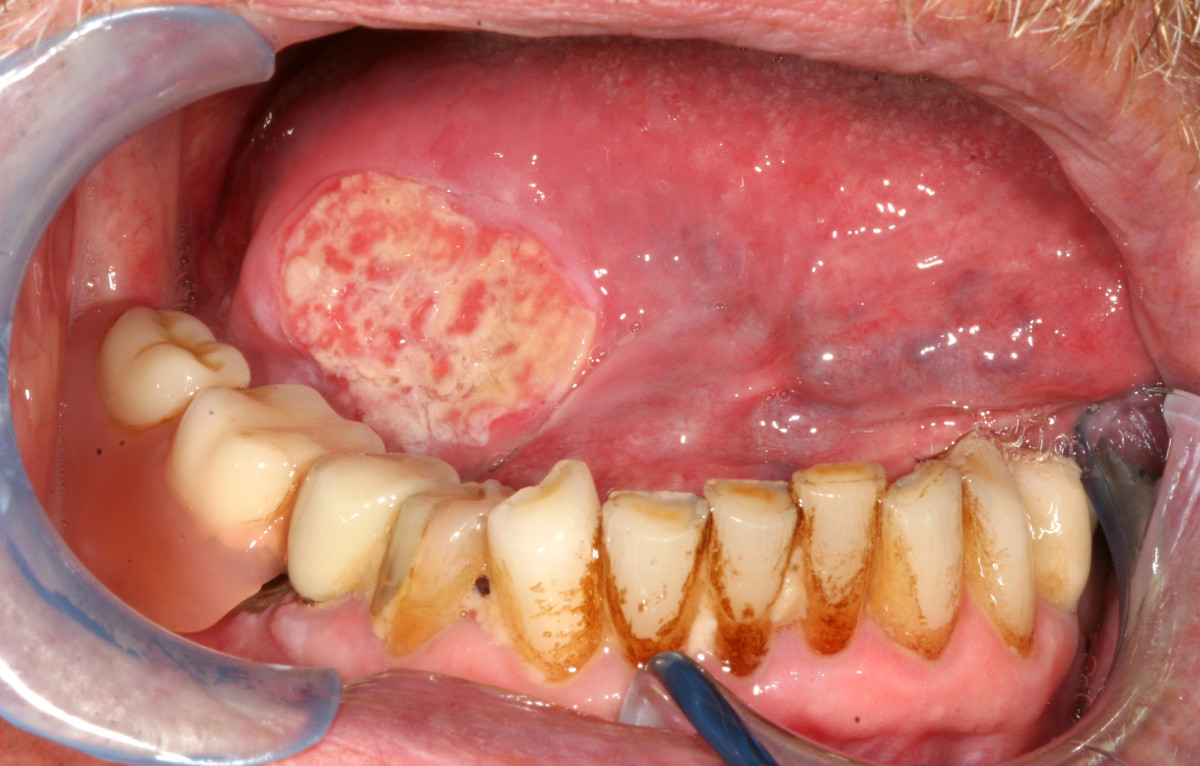

It is generally accepted that oral cancer and especially cancer of the tongue often shows lymph node involvement even in early stages [Figure 11]. The proportion of occult metastases is quoted between 24 and 42%(39)(40)(41). The number of patients with initial lymph node involvement in our study was low compared to other studies(42). Especially the number of patients with bilateral lymphatic spread was surprisingly rare, since bilateral lymph node metastases are observed more frequently by other authors(37)(38). This might be attributed to the reduced proportion of patients in our study with unilateral and especially bilateral neck dissection during initial treatment. However, a regional failure rate in every fifth patient is a clear indicator for too restrictive surgical management of the neck. The reduced survival rates of patients with regional failure shows that a "wait and see" policy on the neck is clearly not advisable. Many authors therefore recommend elective neck dissection even in early stages of tongue cancer when the neck is clinically staged N0(39)(40).

Figure 11 Thumb

Figure 11. Toung carcinoma defect of the right toung in a 64 year-old patient following resection of tumor. The reconstruction is planed with an anterolateral thigh flap (ALT-flap).